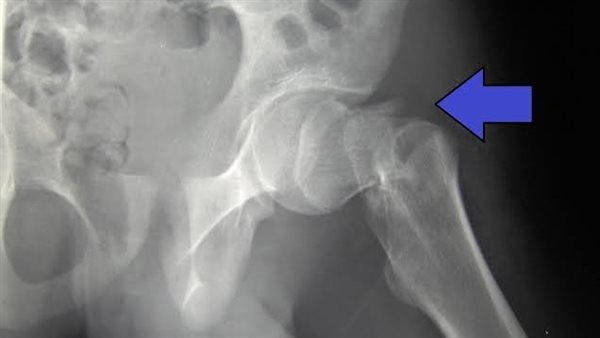

كان الطفل يعاني من كسر بعظم الفخذ الأيمن، وتم تشخيصه بواسطة عينة تحت الأشعة المقطعية من عظام الفخذ ونخاع العظام بواسطة كلا من الدكتور محمد فؤاد، والدكتورة هاجر محسن أخصائي الأشعة التداخلية .

وتم تشخيص الحالة بنجاح (Malignant small round cell tumor)، وذلك بواسطة معمل تحليل الأنسجة بمستشفى النصر التخصصي، ضمن التطور التكنولوجي التي تشهده منظومة التأمين الصحي.